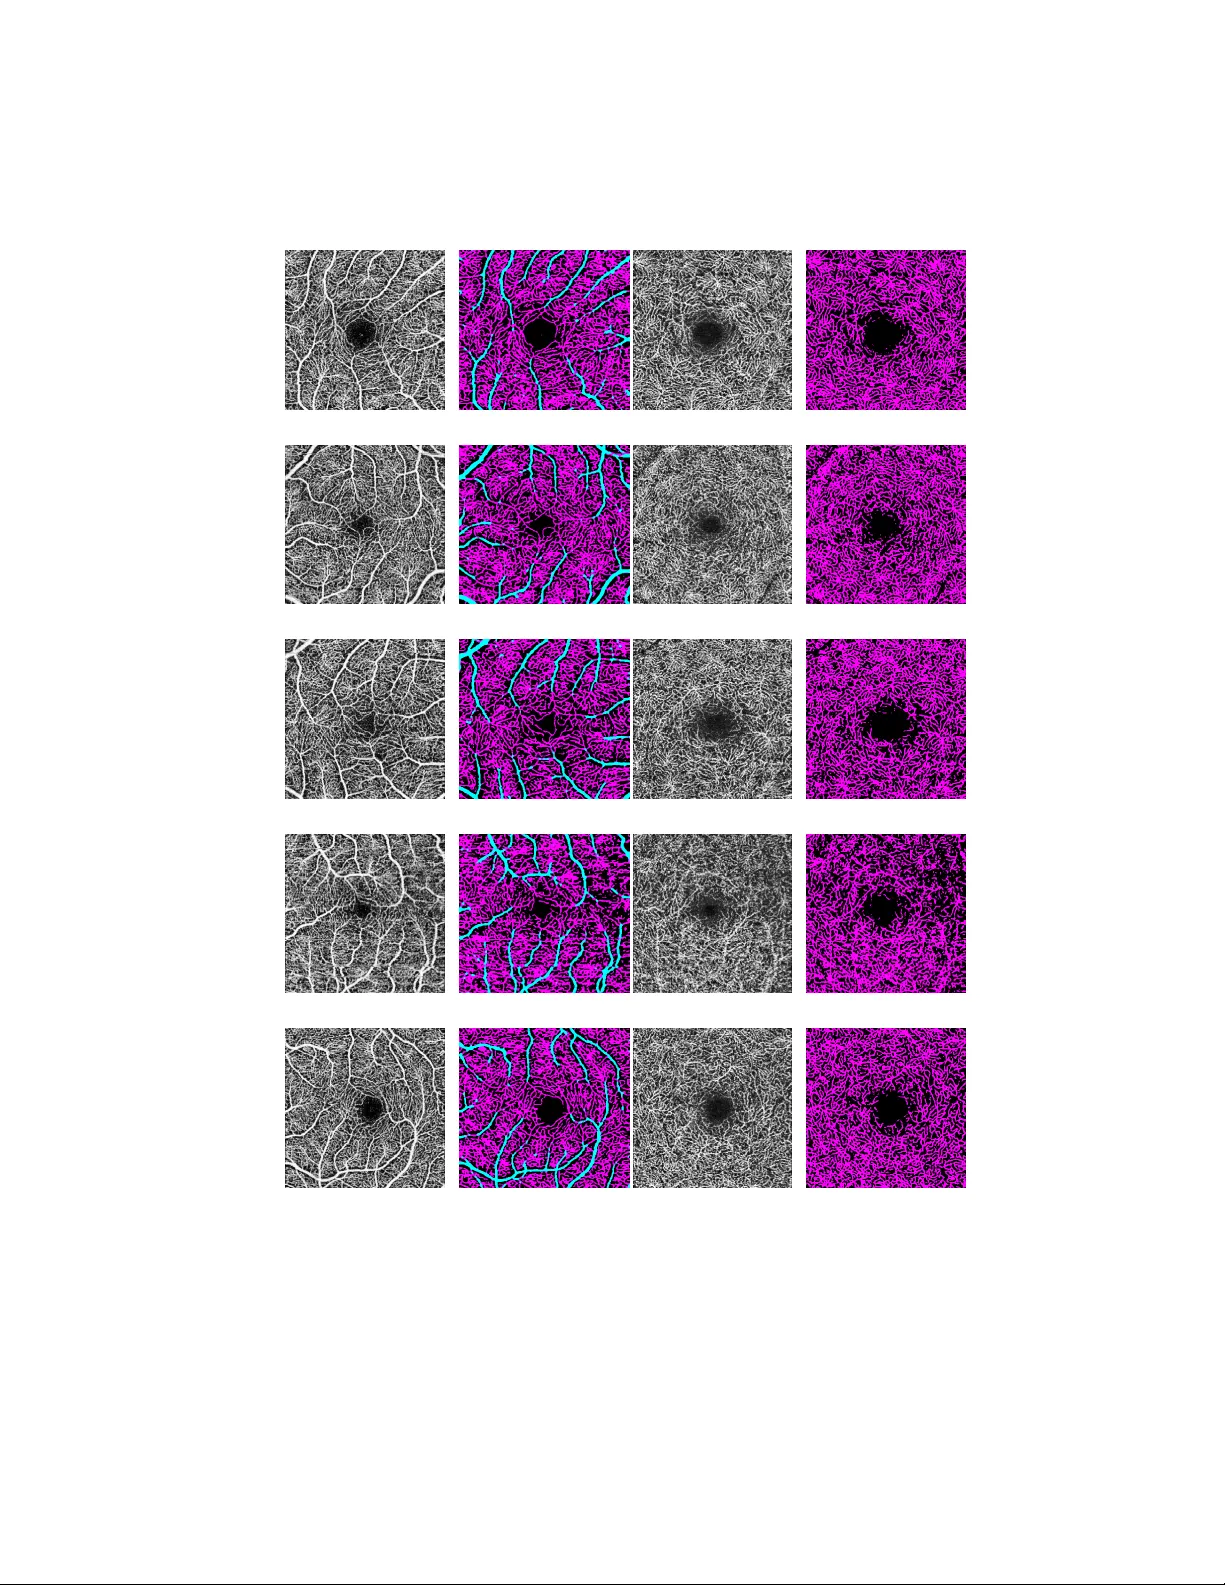

단일 라벨링 이미지(640×640)만을 사용해 딕셔너리를 학습했음에도, SRL과 DRL 모두에서 대혈관과 모세혈관을 명확히 구분하는 결과를 얻었다. 시각적으로는 대혈관은 청색, 모세혈관은 자홍색, 배경은 검은색으로 표시되었다. 실행 시간은 PCA 모델 구축 4.25 초, 딕셔너리 생성 7.01 초, 새로운 이미지에 대한 분할 5.95 초로, 실시간 혹은 근접 실시간 적용이 가능함을 보여준다.